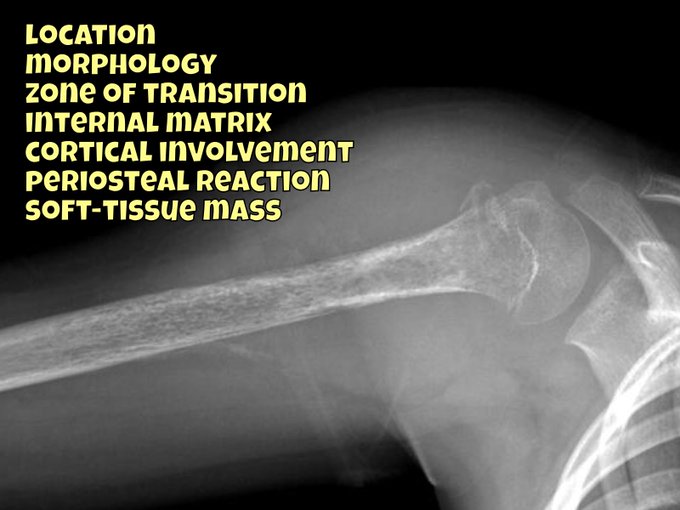

The current featured video is a 7 case Upper Limb X-ray tutorial I recorded during the recent lockdown. Big thanks to my first year registrars for letting the world eavesdrop!

WATCH: https://t.co/HKdZaSa4e3